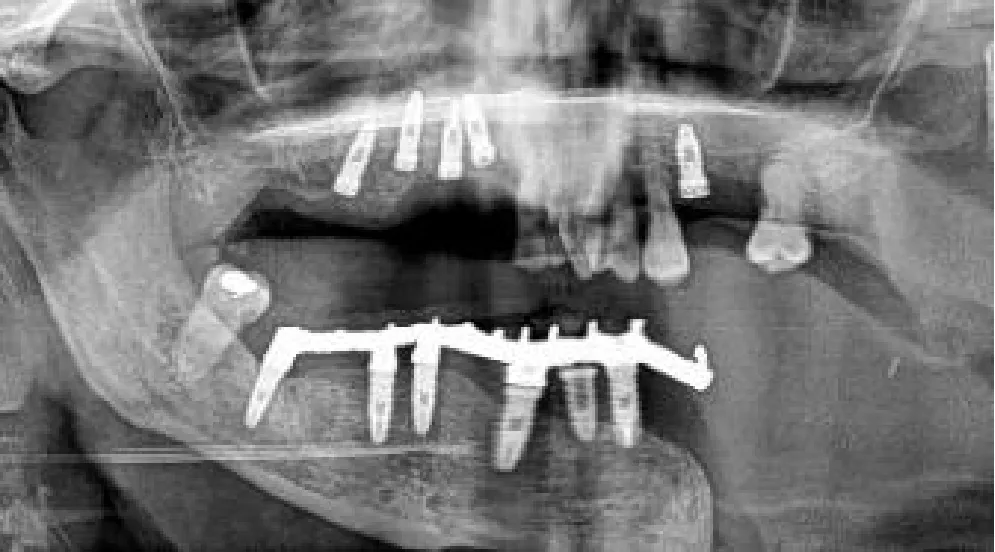

Regarding virtual surgical planning translation to the surgical field, in our initial four patients (Figure 2) we followed a silicone jig tooth-supported dynamic navigated procedure. We built the virtual plan in the NobelClinician-DTX® studio implant software (Nobel Biocare®, Zurich, Switzerland) and manually created a silicone tooth-retained jig to hold the 3D-printed dynamic reference frame by articulating upper and lower jaw plaster impressions on a semi-adjustable articulator. Registration was based on fiducial markers and in some previous foreign bodies attached to the oncologic patient, including in-situ osseointegrated implant heads or fixed osteosynthesis devices, screws, and reconstructive plates.

In those eleven patients, we treated 14 jaws, 3 jaws exclusively with sCAIS (closed transmucosal technique, 13 implants), 4 jaws with dCAIS (13 implants), and the other 7 with a combination of both methods (30 implants). In those 11 navigated jaws, we opened a flap for proper bone visualization and soft tissue remodeling. Adequate bone width control is advisable in extremely narrow alveolar bone cases. Vestibular cortical plate fenestration was noticed in three implants, so we extracted the implants and placed them again in different locations. Those three freehand implants were visually oriented and placed in the best-quality bone that was found available intraoperatively without considering the virtual planning. That is why they were withdrawn from the statistical analysis. We also withdrew our third patient (3 implants) from the analysis, since we did not achieve enough stability of the optical markers. Hence, the navigation procedure was not accurate enough, ending the surgery in a conventional non-guided freehand method. Consequently, the implants were placed with an eye-oriented insertion axis and without considering the prosthetically driven surgical planning. Despite the intraoperative complication, the osseointegration was uneventful in the fibula and we ended with the planned fixed screw-retained prosthesis (Table 1, patient 5, orthopantomogram with the prosthesis in place). Therefore, we withdrew a total of 6 freehand placed implants from our data analysis